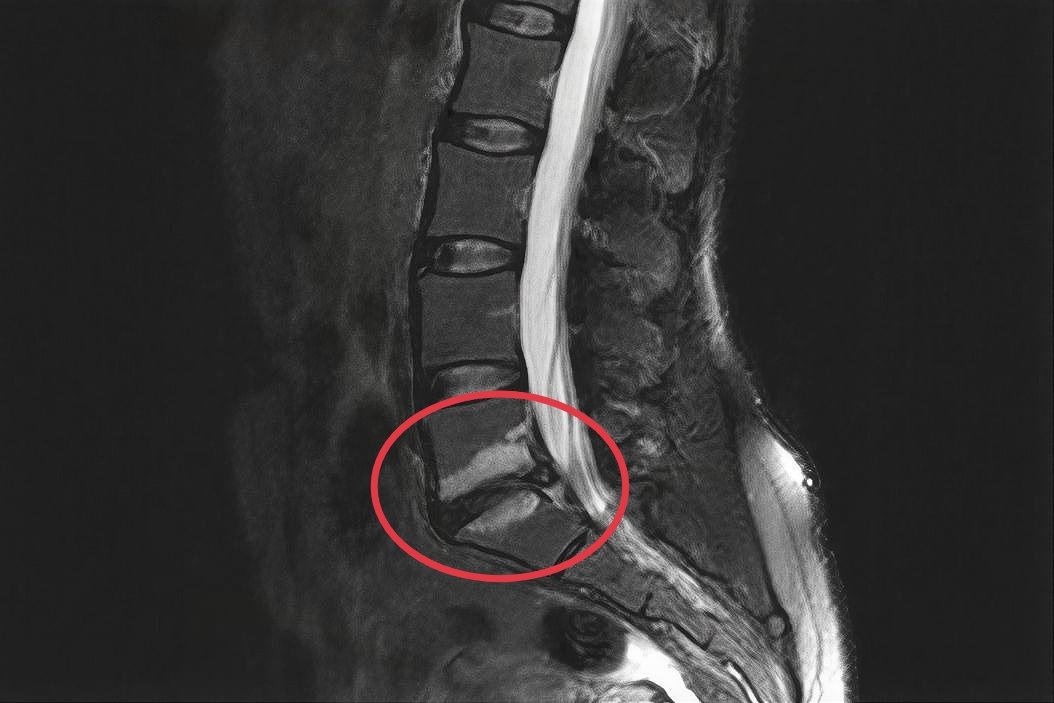

Прежде всего, диагностика должна опираться на данные МРТ, которые помогут определить тип изменений Modic и степень их влияния на состояние пациента. Это позволит разрабатывать более целенаправленные терапевтические стратегии.

Изменения Модик l типа на снимке МРТ

При обращении в клинику, его жалобы включали постоянные ноющие боли, которые усиливались при длительном сидении и определенных физических нагрузках. При проведении МРТ исследования были выявлены изменения Modic типа I (Модик 1), что указывало на наличие воспаления костного мозга.